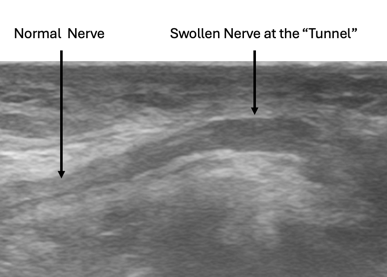

The second image below shows a longitudinal view of the ulnar nerve at the elbow (cubital tunnel). As you can see, the nerve swells as it approaches the tunnel.